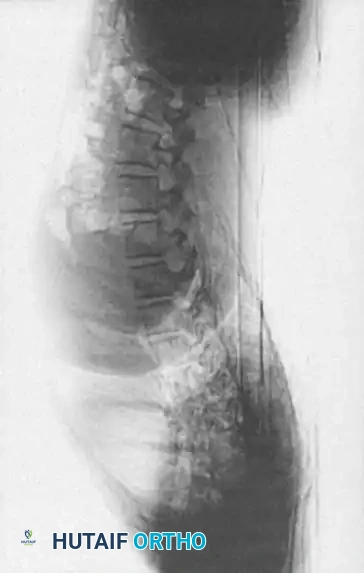

Two-year-old child with type I congenital kyphosis